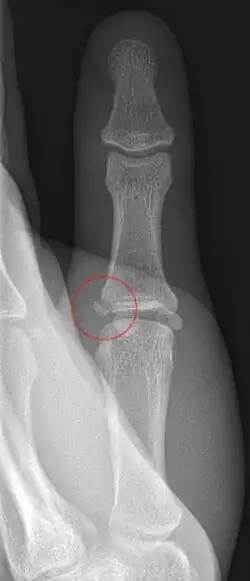

Die Seitenbandruptur des Daumens, im Volksmund auch Skidaumen genannt, ist eine häufige Bandverletzung des Daumens. Durch eine Gewalteinwirkung knickt der Daumen im Grundgelenk nach außen (radial) weg und das innenseitige (ulnare) Seitenband zerreißt. Auslöser ist oft ein Sturz auf die Hand mit abgespreiztem überstrecktem Daumen, sehr häufig beim Skifahren (daher der umgangssprachliche Name). Das Seitenband reißt meist distal nahe am Ansatz an der Grundgliedbasis ab, und gelegentlich kann das gerissene Band unter der Aponeurose des M. adductor pollicis nach proximal hervortreten, was dann als Stener-Läsion bezeichnet wird und nicht reponierbar ist[2]. Manchmal kommt es auch zum knöchernen Bandausriss, wobei dann im Röntgenbild an der ulnaren Grundgliedbasis ein kleines Knochenfragment sichtbar ist.

Nach einer Seitenbandruptur zeigen sich typischerweise eine schmerzhafte Schwellung, oft mit Bluterguss. Dies ist jedoch unspezifisch und tritt ebenso bei einer Distorsion oder einer Fraktur auf. Daher muss ein Knochenbruch insbesondere des Köpfchens des ersten Mittelhandknochens sowie von knöchernen Bandausrissen mittels Röntgenbild ausgeschlossen werden.